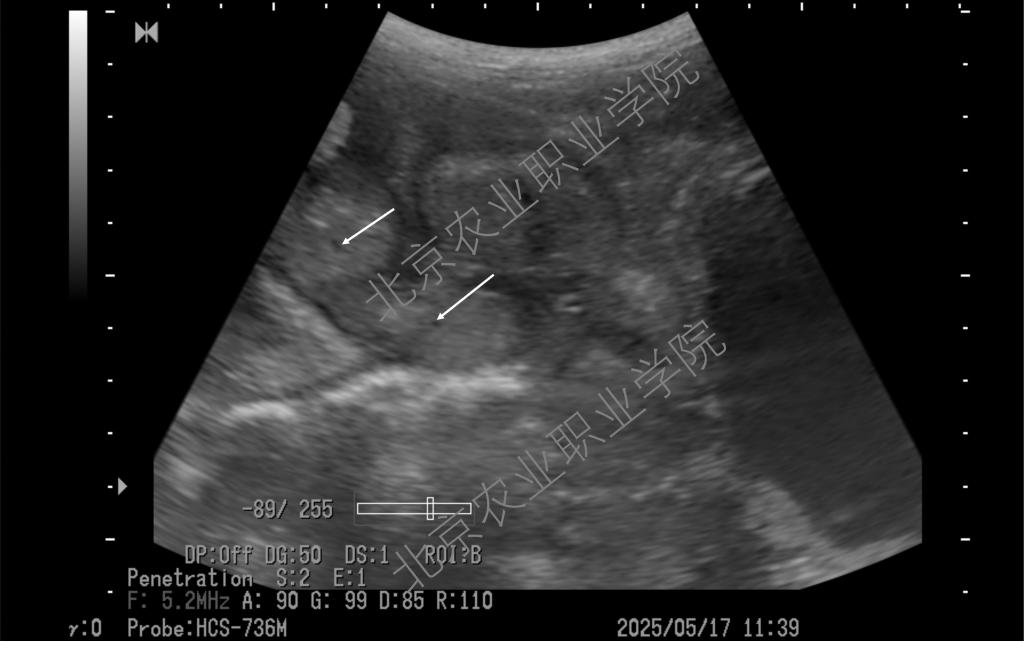

近日,受北京伟杰信生物科技有限公司邀请,动物科技学院兽医超声技术团队为该公司“母猪妊娠21天超声检查技术操作规范”项目提供了重要的技术支撑,并取得重大进展。团队首席专家姜晨副教授梳理了母猪不同体位超声扫查的方法,以便技术人员在不改变母猪体位的情况下做出准确诊断,最大程度上降低怀孕母猪不必要的应激。

近年来,best365姜晨副教授领衔的兽医超声技术团队积极推广超声影像技术在多种动物临床中的应用,并取得一系列技术成果。团队持续探索母猪孕早期超声检查的边界,目前最早可在排卵后第9天确认是否怀孕(可见直径约1mm的卵囊液)。此超声检查技术已达到国际前沿水平,为打开母猪孕初相关的科学研究之门提供了一把金钥匙。